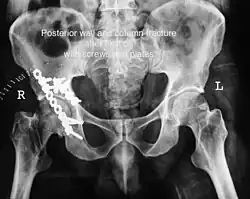

Posterior wall fracture fixed with screws and plate -

The final management depends on the size of the fragment(s), stability and congruence of the joint. In some cases traction for six to eight weeks may be the only treatment required; however, surgical fixation using screw(s) and plate(s) may be required if the injury is more complex. The latter treatment will be called for if bone fragments do not fall into place, or if they are found in the joint, or if the joint itself is unstable.